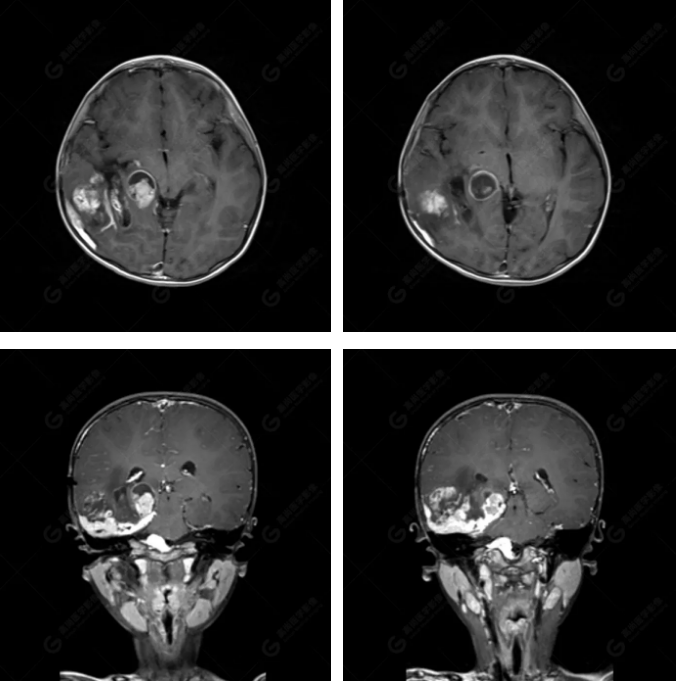

右側(cè)顳葉腫瘤切除術(shù)后(具體不詳):右側(cè)顳部骨質(zhì)不連續(xù)呈術(shù)后改變,右側(cè)顳葉術(shù)區(qū)見片狀長T1長T2信號影,F(xiàn)LAIR呈低信號;術(shù)區(qū)后方右側(cè)顳枕葉見一巨大占位性病變影,邊界欠清,大小約6.2×5.8×4.3cm(前后×左右×上下),信號不均勻,T1WI呈等稍低信號間雜少許高信號,T2WI呈高稍低混雜信號,DWI示部分病灶彌散受限,相應(yīng)ADC圖減低,磁敏感序列見部分呈極低信號,增強掃描可見明顯不均勻強化,鄰近硬腦膜及小腦幕增厚并明顯強化;另延髓右前方及右側(cè)橋小腦角區(qū)見一不規(guī)則形異常信號影,大小約3.2×1.3×3.7cm(左右×前后×上下),呈長T1稍長T2信號,F(xiàn)LAIR呈等信號,DWI未見受限,增強后明顯均勻強化,鄰近腦膜明顯強化。鄰近腦實質(zhì)及右側(cè)顳角明顯受壓;左側(cè)大腦半球未見局灶性信號異常,中線結(jié)構(gòu)稍左移。

右側(cè)顳葉腫瘤切除術(shù)后:現(xiàn)術(shù)區(qū)后方右側(cè)顳枕葉及延髓右前方占位,右側(cè)顳枕部硬腦膜及小腦幕明顯強化,結(jié)合既往影像資料,考慮為胚胎源性惡性腫瘤,如非典型畸胎樣/橫紋肌樣瘤(AT/RT)或原始神經(jīng)外胚層腫瘤(PNET)。